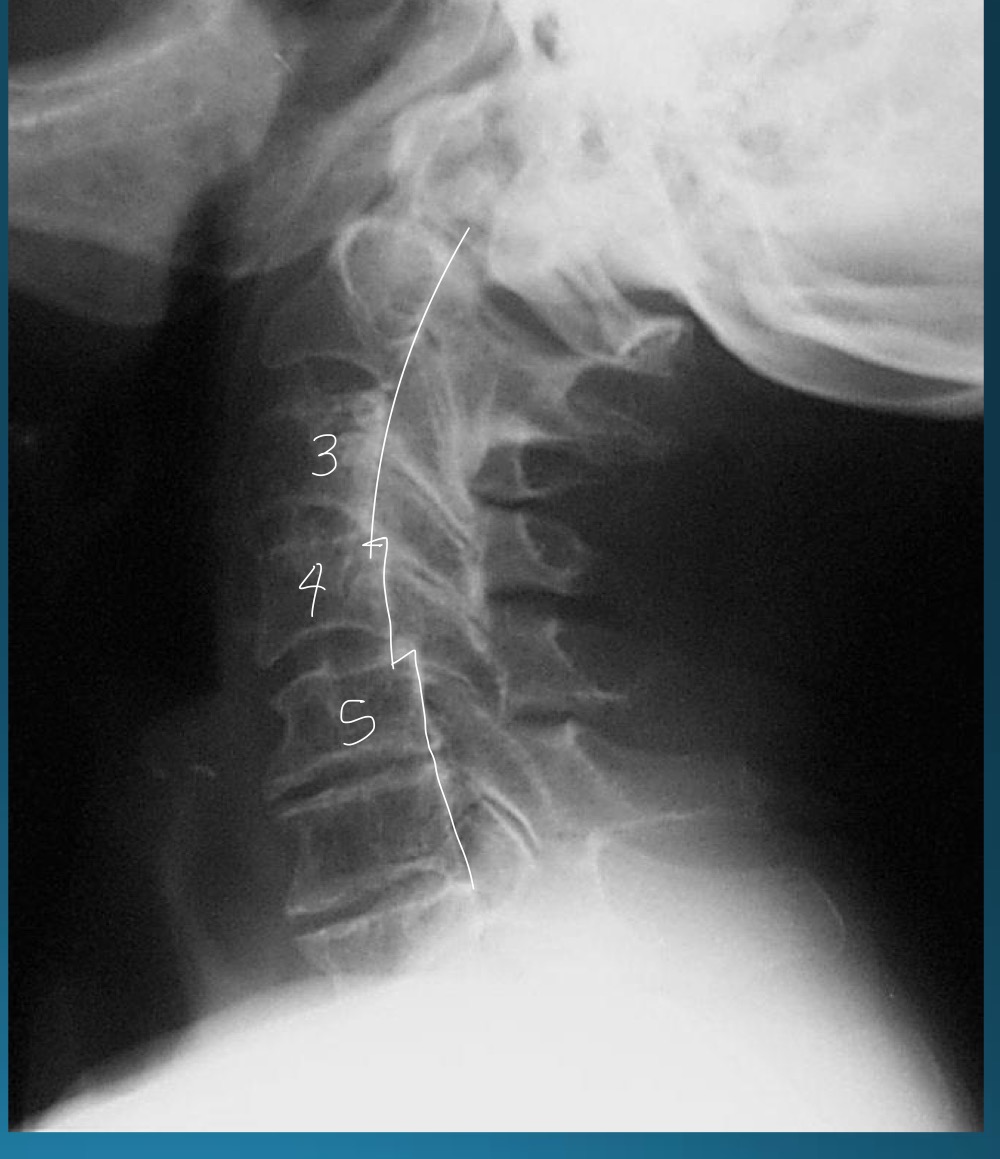

what are the findings in this image?

facet arthrosis